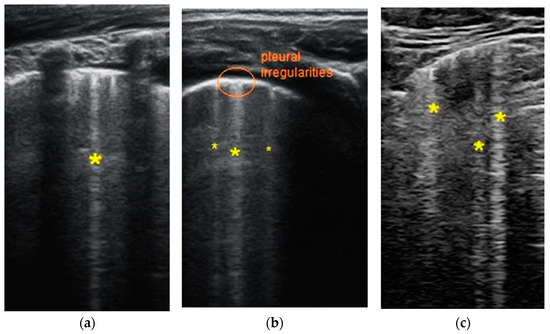

- Transverse physiologic A-lines that depict healthy parenchyma;

- Isolated/sparse vertical B-lines are equivalent to interstitial edema;

- Confluent vertical B-lines correspond to alveolar edema;

- Subpleural/peripheral consolidations;

| LUSS = 0 Points | LUSS = 1 Point | LUSS = 2 Points | LUSS = 3 Points |

|---|---|---|---|

| Normal/physiological A-lines | More than 2 B-lines (sparse B-lines) with associated pleural abnormalities | Coalescent or confluent B-lines | Large peripheral consolidation (wider than 1 cm) in association or not with air bronchogram |

| One or two B-lines per intercostal space | ‘White-lung’ aspect or small peripheral consolidation (smaller than 1 cm) |